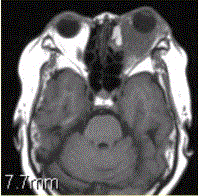

患者女,64岁,左眼突出5年余。查体左眼球前突6mm,眼球运动自如,眼底无异常,下睑扪及边界不清、质软的肿块,视力正常,MR表现如下图。临床拟...

问题 患者女,64岁,左眼突出5年余。查体左眼球前突6mm,眼球运动自如,眼底无异常,下睑扪及边界不清、质软的肿块,视力正常,MR表现如下图。 临床拟诊为

选项 A.眶内炎性假瘤 B.眼型Grave病 C.黑色素瘤 D.转移瘤 E.眼眶海绵状血管瘤 F.弥漫型淋巴管瘤

答案 A